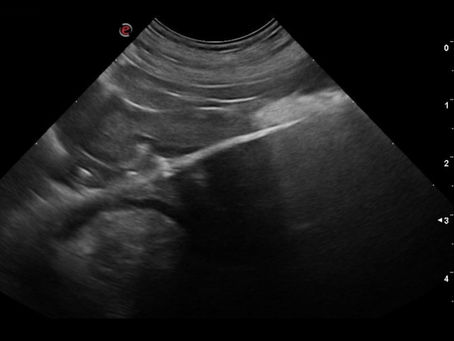

Pyonephrosis in a dog caused by ureteral obstruction

Hydronephrosis, a condition characterized by the dilation of the renal collecting system, often results from an obstruction that impedes...